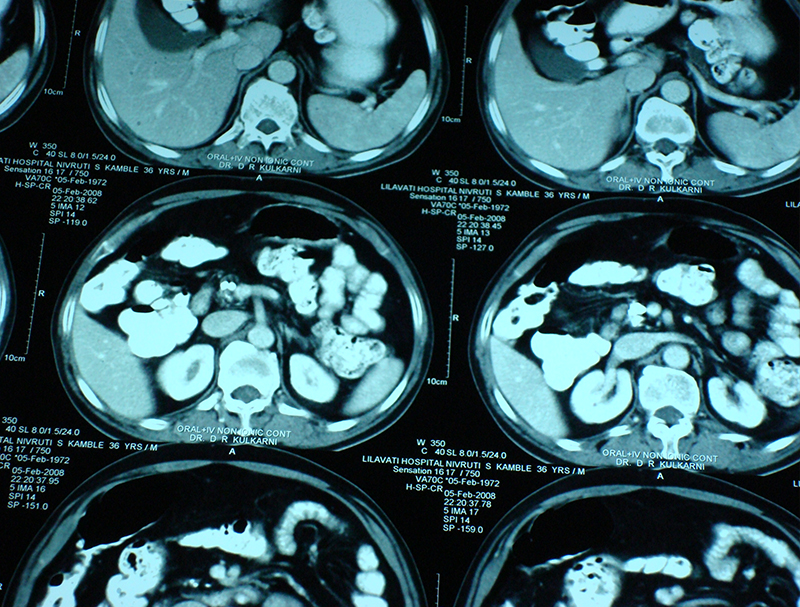

30 year old young lady with chronic pancreatitis, narrowing (stricture) of the pancreatic duct in the head and tail of pancreas and obstructing stone in the tail portion of the pancreatic duct presented to us with a recent attack of mild acute pancreatitis. She had undergone pancreatic duct stenting 3 times before this and stent migrated out of the duct at the last time following which she had acute pancreatitis. She was thoroughly evaluated with CT scan and MRI of abdomen. It showed that the duct had dilated irregularly in head and body of the pancreas and a stone was lodged in the tail. So she had disease both in the head and tail. She underwent a distal pancreatosplenectomy for the tail disease and a pancreaticojejunostomy (Head coring—Frey procedure) for the disease of the head and body of pancreas. She recovered well however the recovery was prolonged due to intra-abdominal infection caused by organisms in the infected pancreatic fluid. Infections originated from the pancreatic stents, were resistant to routine antibiotics and needed expensive drugs for infection control.

25 year old male presented with abdominal pain due to chronic calcific pancreatitis. He had had multiple previous endoscopic stent placement procedures & external shock wave treatment (ESWL) attempts to break & remove pancreatic stones and pancreatic duct stenting. He was investigated and later operated. A Frey procedure was done wherein the inflamed and stone filled core in the head of pancreas was removed, duct was widely opened along the head, neck, body and tail of pancreas. All the ductal stones were removed and multiple narrowing were opened. A loop of intestine was then joined with the pancreatic duct. He recovered uneventfully. He is fine for last 8 years and has not required any long term painkillers or had any episodes of pancreatitis. His dose of pancreatic enzyme supplements has also come down.

40 year old male with chronic calcific pancreatitis due to alcohol, continuous abdominal pain and weight loss underwent surgery (head coring and pancreaticojejunostomy). He did not have any previous stenting procedures. Patient recovered smoothly and was discharged on 6th day after surgery and has remained well for last 6 years.